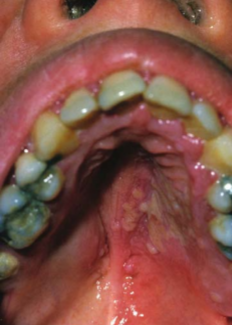

Döküntüler ağız ve genital alanda mukozada da görülebilmektedir.